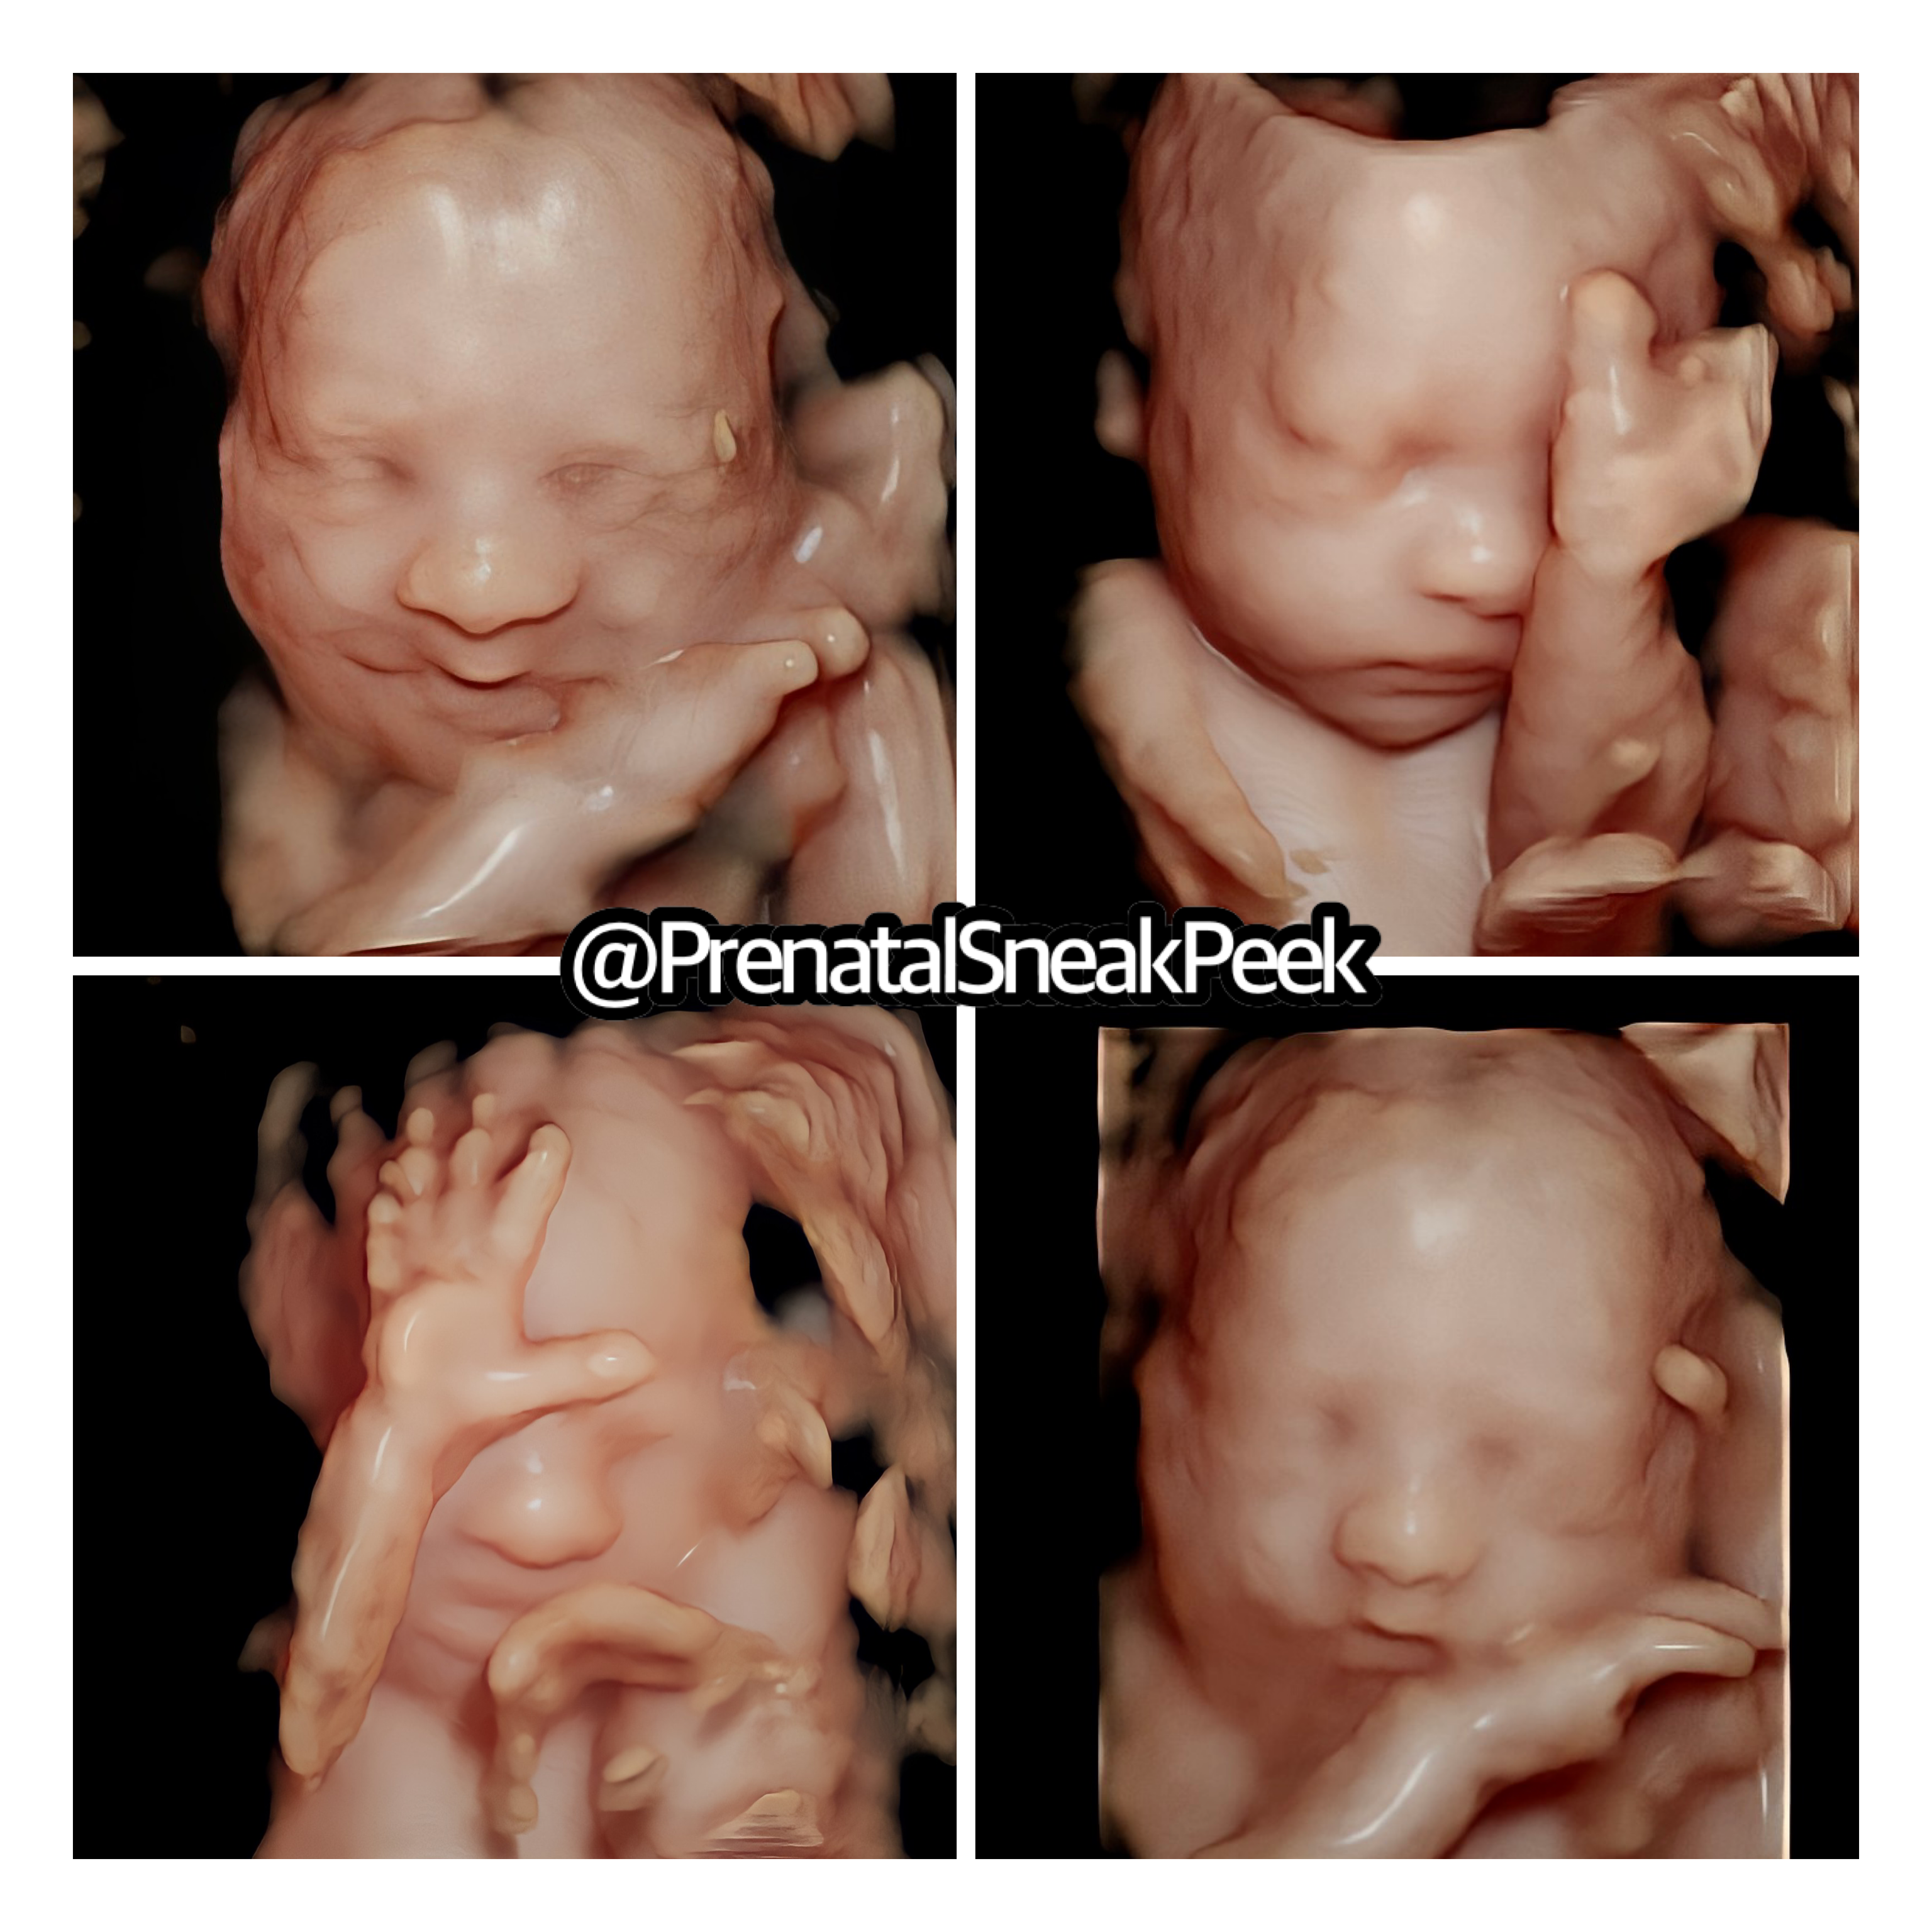

ABOUT PRENATAL SNEAK PEEK

Prenatal Sneak Peek is an elective mobile ultrasound company that provides ultrasounds in the comfort of your home. It is owned and operated out of Bel Air MD. Owner, Kelly Wargo, RDMS is a Registered Diagnostic Medical Sonographer with a specialty certification in OB. She has over 15 yrs. experience in the field of ultrasound. Kelly is the sole operator of her business; therefore, you will get the same quality every time! She also has a heart for saving babies, providing ultrasound services part-time to Options@328 a nonprofit located in Baltimore City.